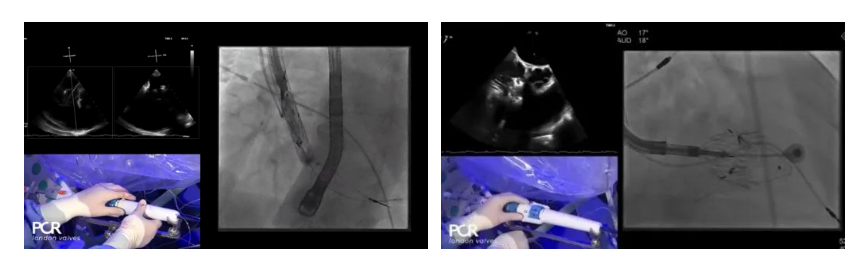

手術(shù)在全麻狀態(tài)下開展,采用經(jīng)右側(cè)頸靜脈入路的方式將輸送器送入患者心臟內(nèi),在TEE及DSA引導(dǎo)下調(diào)整輸送器頭端角度,使得輸送器與三尖瓣瓣環(huán)平面垂直。在輸送器進(jìn)入右心室后釋放室間隔錨定裝置,而后釋放瓣葉夾持件(2個(gè)耳片結(jié)構(gòu))成垂直狀態(tài)。在TEE及DSA確定夾持件固定至三尖瓣葉根部且位于右室側(cè)后釋放人工瓣心房側(cè)盤片。隨后調(diào)整瓣膜同軸性以及室間隔錨定件位置(貼合室間隔),前推藏針管并固定,進(jìn)而釋放室間隔錨定裝置,并再次確認(rèn)瓣膜位置、穩(wěn)定性及同軸性,合攏輸送鞘后撤出輸送器,完成LuX-Valve Plus人工三尖瓣瓣膜的植入。